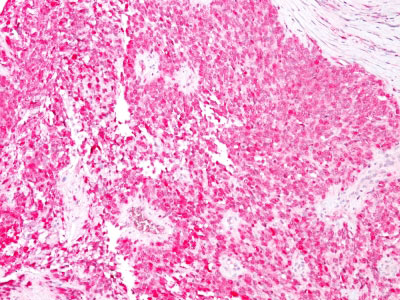

Formalin--paraffin human Melanoma stained with S100A1 Monoclonal Antibody (4C4.9) (AEC Chromogen)